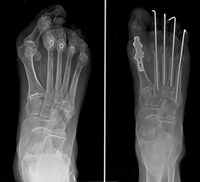

If the RA has progressed and the lesser toes (two through five) have dislocated, a complex operation to minimize the pain and restore the shape of the foot may be recommended. The operation involves fusion of the big toe and removing a portion of bone of each of the metatarsals. This surgery removes the prominent bone on the bottom of the foot that is a source of the pain and allows the toes to re-align into a better position.

To fix the bend in the toes themselves, the surgeon may suggest cutting a tendon or removing a small portion of bone of the toes to allow them to straighten. Pins that stick out of the foot are temporarily required and will be removed in the office after healing takes place.

(Left) RA of the forefoot. The big toe is deviated and crosses over the second toe, a typical appearance of a bunion. The lesser toes (two through five) are dislocated, resulting in painful and severe claw toes. (Right) This x-ray taken immediately after fusion of the big toe shows that the prominent bones on the ball of the foot were removed and the claw toes were corrected. The pins hold the toes in place while the soft tissues heal. The pins are removed in the office after 4 to 6 weeks with minimal discomfort.